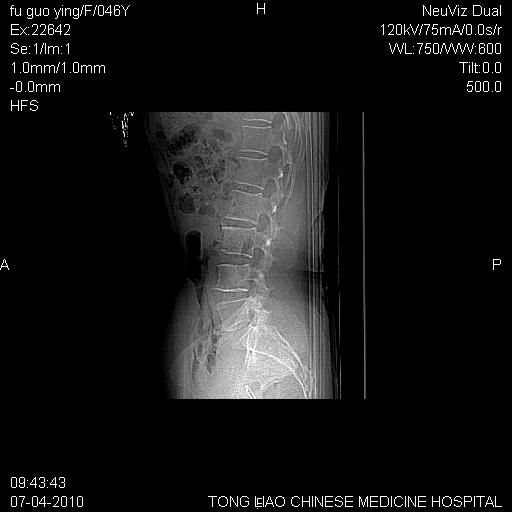

标题: CT27489:患者腰疼,其余椎体未见异常! [打印本页]

标题: CT27489:患者腰疼,其余椎体未见异常!

女性46岁,左髂骨溶骨性破坏+软组织肿块,考虑转移瘤,腰椎为退变/增生硬化/软骨下骨囊变。